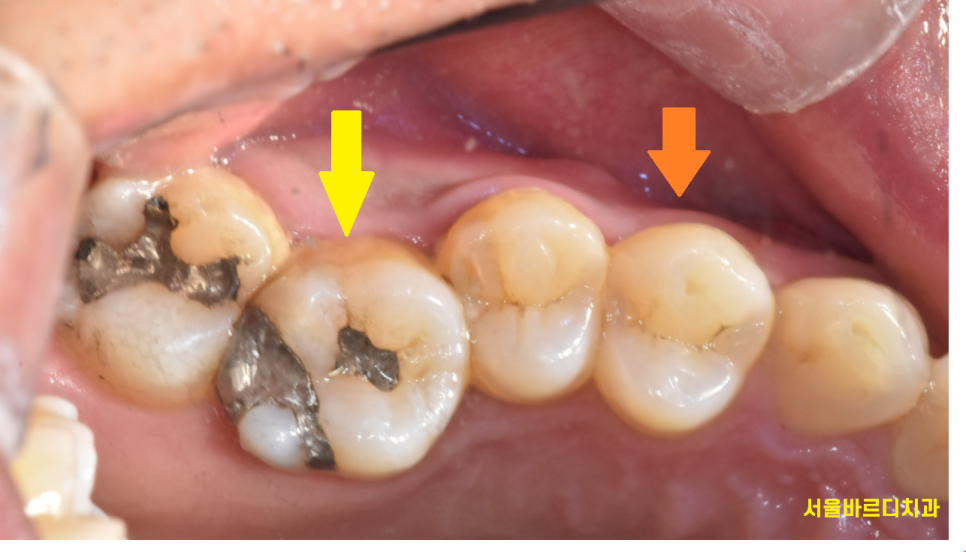

여기서 질문을 드릴께요~!

240527

노란색 화살표

그리고 주황색 화살표

두개 치아 중에 충치가 있는 치아는

무엇일까요??

정답은....!!!!

주황색 화살표입니다.

검은 점처럼 보이는 충치인데요.

그렇지만 대반전은..?

치료를 안해도 되는 충치이다~!

번외편 아말감은 충치가 아닙니다.

사진속 두분의 환자분들 모두

아말감 치료를 하셨습니다.

요즘은 잘 쓰이지 않지만

예전에는 많이 쓰였던 재료인데요.

은색깔이다보니

충치로 오인하기 쉽지만

이것은 재료 본연의 색깔이

검정색이라 그렇지

충치는 아닙니다!

(제발 속지 마세요~~)

아 물론 아말감 주변으로 충치가 있을 수 있는데

이것도 변색인지

충치인지 분간이 필요해요!